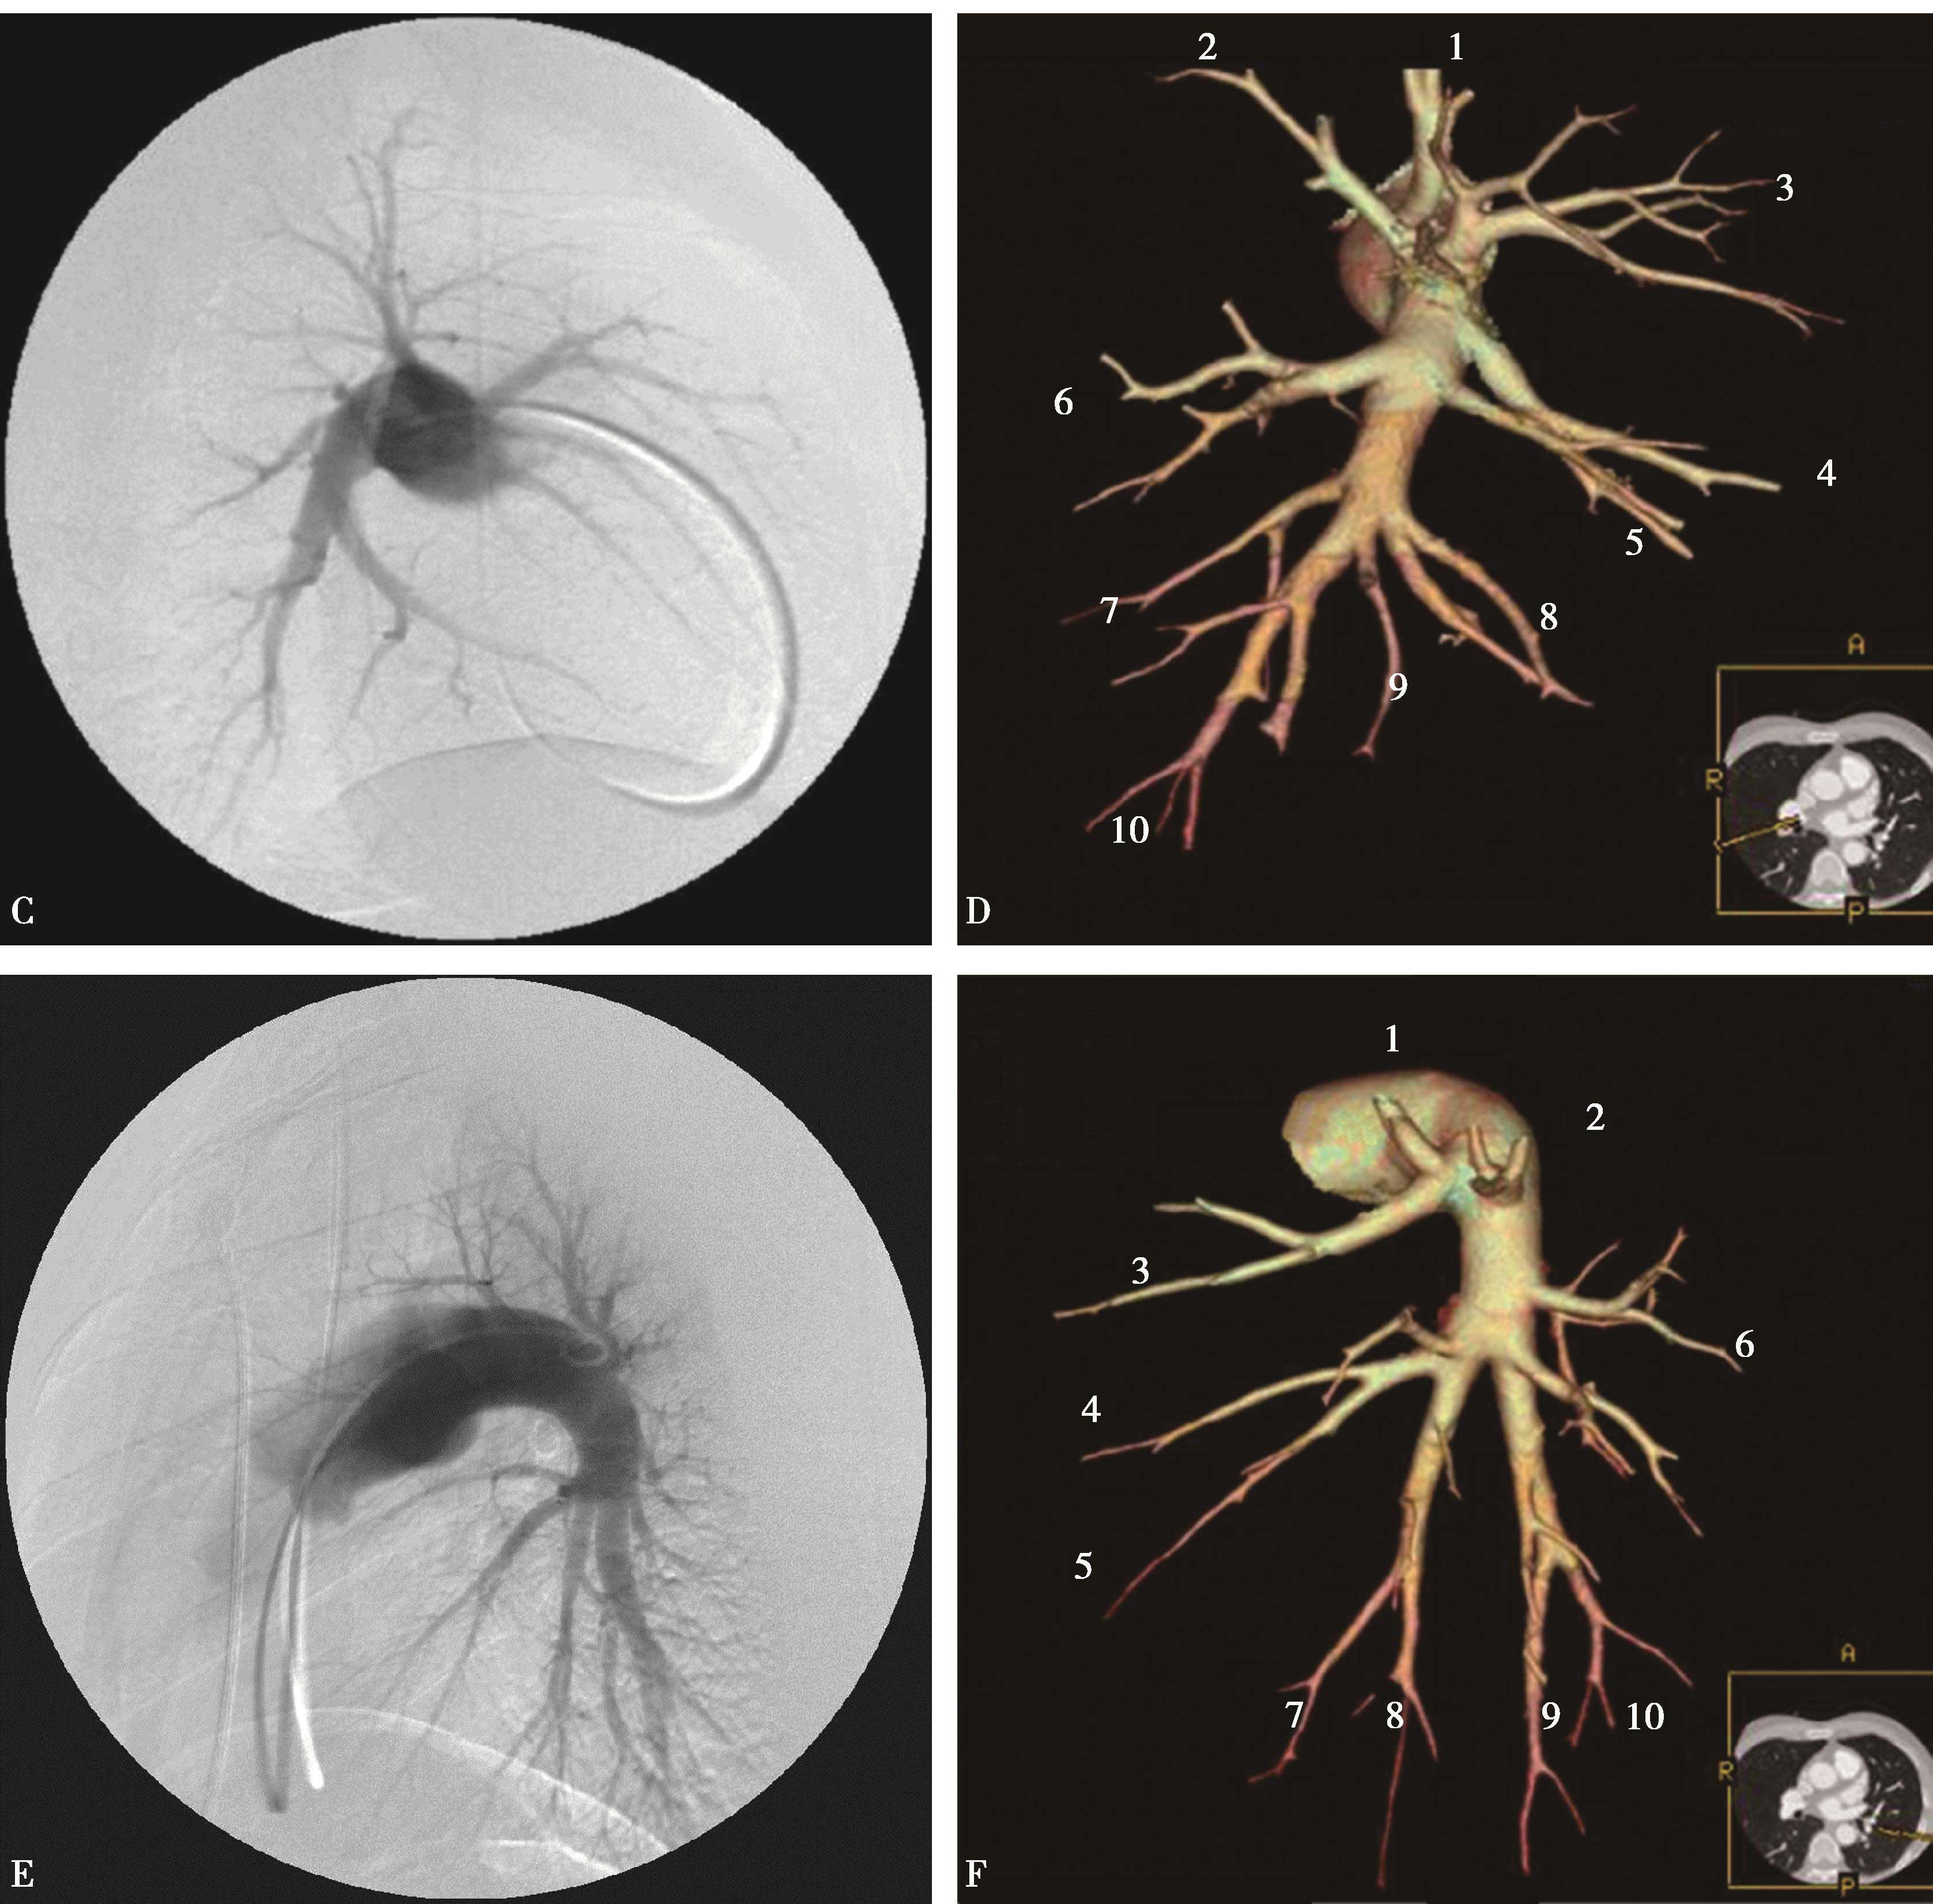

3.容积再现(VR)(图8-2-9)

图8-2-9 肺动脉容积再现与肺动脉DSA对照图

肺动脉DSA(ACE):A.肺动脉DSA(冠状位);C.右肺动脉DSA(矢状位);E.左肺动脉DSA(矢状位)。肺动脉容积再现(BDF):B.肺动脉VR(冠状位),D.右肺动脉VR(矢状位),F.左肺动脉VR(矢状位)。上叶:1.尖段;2.后段;3.前段。(右肺)中叶:4.外侧段;5.内侧段。(左肺)舌叶:4.上舌段;5.下舌段。下叶:6.背段;7.内基底段;8.前基底段;9.外基底段;10.后基底段